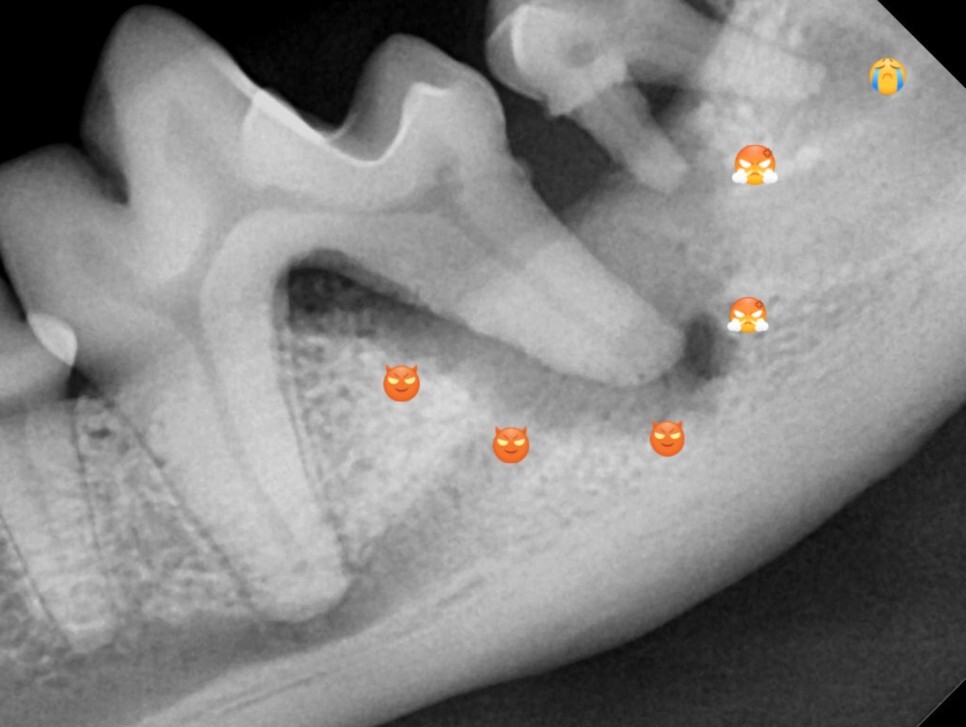

방사선 검사상 같은 부위에 치주염이 있는 것을

확인할 수 있었습니다. 또한 바로 뒤의 두 번째 어금니에도 병변이 확인되었습니다.

이 아이의 경우 병변이 너무 많이 진행되어서 첫 번째

어금니와 두 번째 어금니 모두 발치를 진행하였습니다.